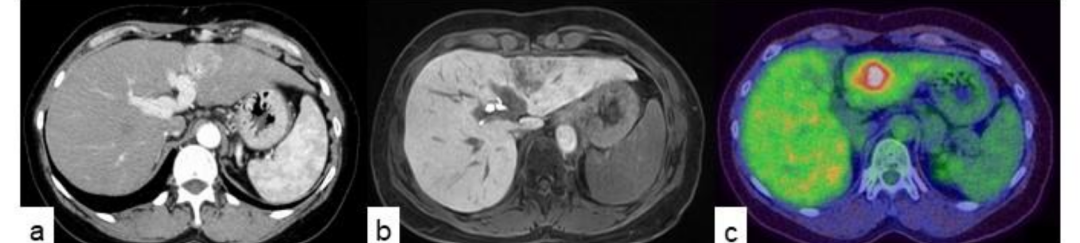

动态计算机断层扫描(CT)显示肝侧段有一个直径40毫米的肝脏肿块,在动脉期有强烈均匀的强化;增强磁共振成像显示肝胆期高强度;PET-CT扫描显示肿瘤摄取了明显的氟脱氧葡萄糖。未见肝内、肝外转移,但未见门静脉外支,提示门静脉肿瘤血栓形成。